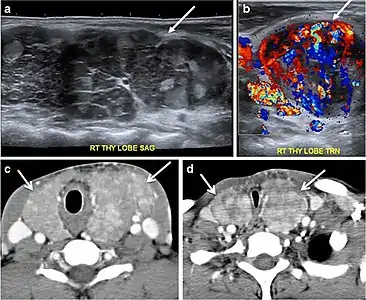

Fig. 14. A 19-year-old male patient known to have multi-nodular goiter and FNA, showing underlying Hashimoto's thyroiditis. a, b Sagittal and transverse greyscale and colour Doppler ultrasound of the neck demonstrate a hypoechoic enlarged right thyroid lobe with small hyperechoic regenerative nodules and marked hypervascularity (white arrows). c, d Enhanced axial CT scan images of the neck demonstrate a heterogeneously enhancing and enlarged thyroid gland, left more than right lobe, and the trachea is markedly narrowed.[1] Fig. 14. A 19-year-old male patient known to have multi-nodular goiter and FNA, showing underlying Hashimoto's thyroiditis. a, b Sagittal and transverse greyscale and colour Doppler ultrasound of the neck demonstrate a hypoechoic enlarged right thyroid lobe with small hyperechoic regenerative nodules and marked hypervascularity (white arrows). c, d Enhanced axial CT scan images of the neck demonstrate a heterogeneously enhancing and enlarged thyroid gland, left more than right lobe, and the trachea is markedly narrowed.[1]